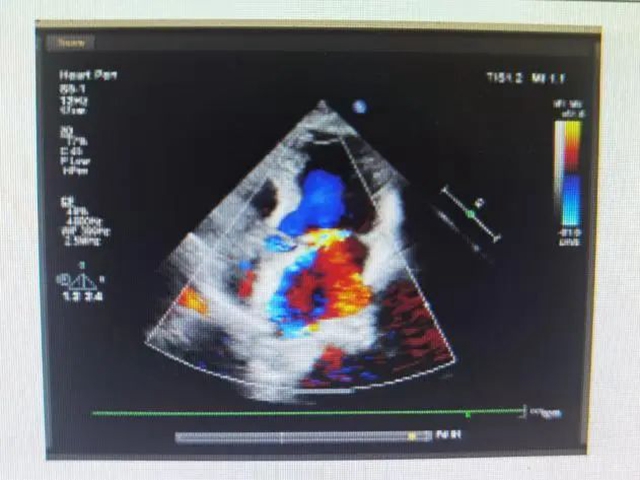

“1次手术就能解决问题!”  “创伤小、出血少、恢复快,真不错!”  到底是啥手术?  极致微创!全球最细且“长眼睛”的针状肾镜!  1.4毫米“针孔”通道碎石  近日,在西南医科大学附属中医医院手术室里,泌尿外科副主任,兼泌尿系结石诊治...